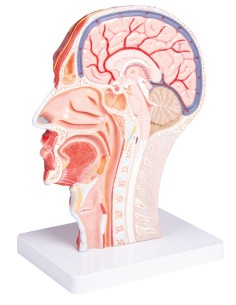

Découvrez le monde de l'anatomie avec des modèles anatomiques de précision

Bienvenue sur Tuttoanatomia.it, le portail de référence en Italie pour l'achat de modèles anatomiques, de posters, de lits portables, de simulateurs médicaux et de littérature spécialisée. Grâce à nos modèles anatomiques de pointe de 3B Scientific et Erler Zimmer, nous offrons une expérience d'apprentissage inégalée.

Des modèles anatomiques détaillés pour tous les besoins

Du crâne en 22 parties à verrouillage magnétique aux modèles de colonne vertébrale, des modèles d'articulation aux modèles de cœur, chaque pièce de notre collection est conçue pour une immersion totale dans l'étude de l'anatomie humaine. Nos modèles, réalisés à partir de scans d'os réels, garantissent une expérience tactile authentique et une fidélité de poids presque identique aux originaux.

Des outils pédagogiques innovants pour l'enseignement et la pratique de la médecine

Indispensables aux étudiants comme aux professionnels, nos modèles anatomiques sont des outils pédagogiques qui permettent d'observer les structures anatomiques avec précision, en évitant les dissections ou les études invasives. Ils sont également utiles pour expliquer les pathologies aux patients, ce qui rend la communication plus efficace et permet de gagner un temps précieux.